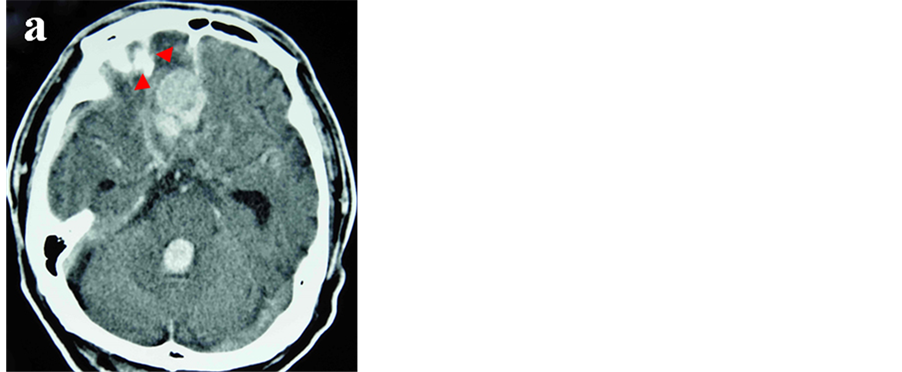

A 74-year-old man was transferred to our institute with severe impairment of consciousness. On admission, his Glasgow Coma Scale was 4 (E1V1M2) and he exhibited partial loss of brain stem reflexes. CT scan showed a large hematoma in the right frontal lobe with subdural and intraventricular hemorrhage. A more noteworthy finding was that suspicious vascular dilatation was located next to the intracerebral hematoma (Figure 1). Digital subtraction angiography (DSA) disclosed the presence of the dural arteriovenous fistula (dAVF) at the right anterior cranial fossa and fed mostly by the bilateral anterior ethomoidal arteries and partially by the falcine branch of the left middle meningeal artery, and the dAVF drained into the frontal cortical vein with a large venous pouch which coursed to the superior sagittal sinus (Figure 2).

Figure 1. CT scans without contrast medium (a), (b) revealing an intracerebral hematoma with subdural and intraventricular hemorrhage and suspicious vascular dilatation (arrowheads).